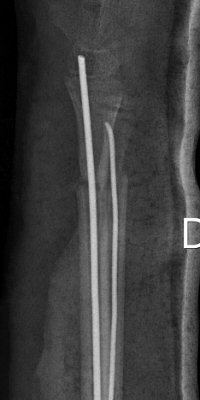

Monteggiafraktur: fraktur på ulna och samtidig luxation av caput radii. Man är inte helt överens om ulnafrakturen ska vara i den proximala tredjedelen [2] eller proximala två tredjedelarna av ulna [3]. Radiushuvudet kan också vara frakturerat istället för luxerat [2].

Monteggiafraktur, opererad med TEN-spik